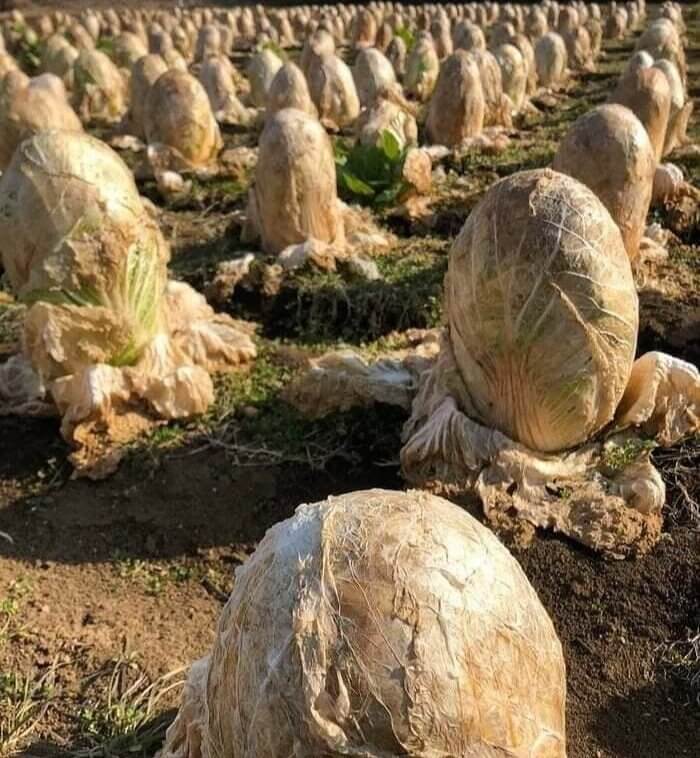

Don’t Worry, This Is Perfectly Normal

Without a title on this image, your imagination might run wild, trying to explain the peculiar sight of numerous small skeletons within one large body. However, once you understand the context, it becomes quite incredible. The image reveals multiple sets of bones all compressed into a small space, and surprisingly, it’s entirely natural. What you’re seeing is a pregnant dog, and those little skeletons represent the upcoming arrival of a litter of puppies.